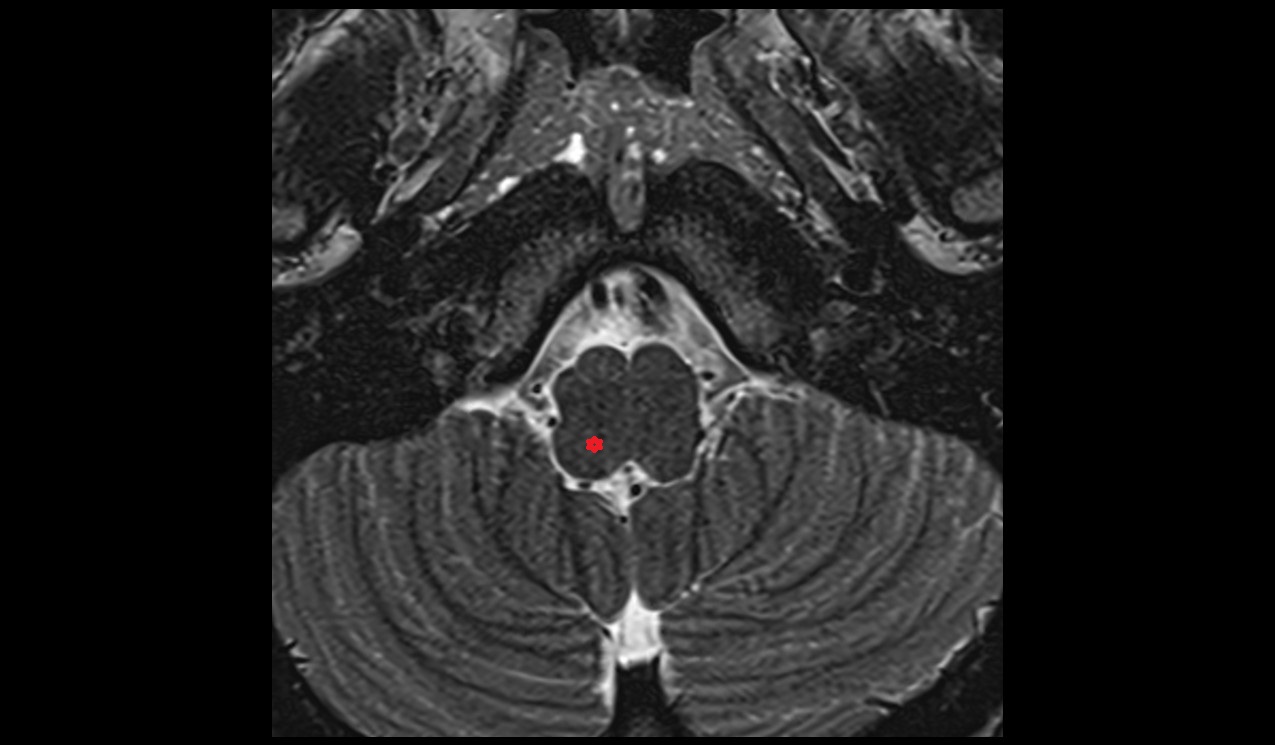

- Cerebellum

- Dentate nucleus